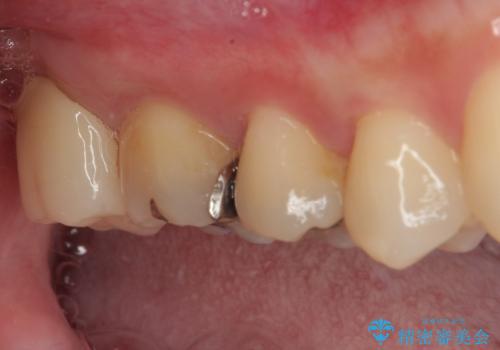

矯正治療により処置が可能な位置に歯が移動したため、オールセラミッククラウンにて補綴治療を行うこととしました。

歯列が移動したとはいえ、左右ともに後方傾斜しており、むし歯の除去、形成(形を整える)、型取りの全てが非常に困難な処置となりました。

セラミッククラウンの適合はレントゲン写真からも分かる通り、境界がぴったりと合った、高適合のものとなりました。